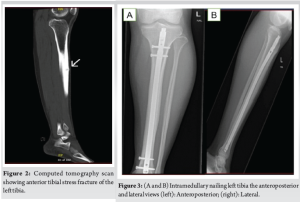

A 26-year-old male professional football player presented to us in the outpatient clinic in July 2024, on wheelchair with the complaint of bilateral shin pain over the past 4 months, localized on the anterior aspect of both legs. The pain was initially mild and worsened during playing football, followed by a constant pain on the left side, which started affecting his sleep and his routine activities. In addition, he complained of mild discomfort on his right leg. He had no history of any recent trauma and other joints or extremity pain in the past, but claimed an increase in intensity of pain while playing football. He had previously used anti-inflammatory medications, calcium, and activated cholecalciferol supplements, and underwent 8 sessions of physiotherapy. During physical examination, inspection revealed normal gait and normal alignment of both lower limbs and there was mild tenderness left mid leg and absent tenderness on the right side on palpation. The range of motion of associated joints and spine was within normal limits. Sensory and motor of each lower limb was normal and comparable. Plain X-ray of left leg (Fig. 1) demonstrated abnormal density in the middle left tibial shaft anteriorly, while right tibia X-rays were inconclusive. Based on X-ray results, the possibility of osteomyelitis in the left tibia was considered, and all inflammatory markers (C-reactive protein, erythrocyte sedimentation rate) were sent, revealing normal levels, which excluded any infections. In addition, endocrine/metabolic workup (Vitamin D, Calcium, parathyroid hormone, thyroid-stimulating hormone, and testosterone) was done and was in normal limits. A computed tomography (CT) scan confirmed left tibia anterior shaft stress fracture (Fig. 2). After reviewing the patient’s history, review of all medications, and thorough examination, including a careful biomechanical assessment and scanning results, a diagnosis of a stress fracture in the left tibia was made. Due to a lack of improvement with trial of conservative management on the left side over the past 4 months, a decision was made to proceed with intramedullary nailing on the left tibia while continuing conservative treatment on the right side, as the X-rays were unremarkable. Post-operative recovery of the patient was unremarkable, and he was allowed weight bearing as tolerated under the supervision of a physiotherapist (Fig. 3). At 3 months, he presented to the outpatient clinic as a follow-up case, with minimal symptoms in his left tibia. However, he expressed ongoing discomfort and mild pain in his right leg, which he claimed partly alleviated with analgesics and avoiding exertional activities. Due to ongoing pain on his right side, right leg X-rays were performed that revealed suspicion of anterior cortex stress fracture (Fig. 4). Consequently, an MRI was performed, which displayed a low signal on T2-weighted imaging with cortical thickening and bone marrow edema, confirming anterior tibial stress fracture (Fig. 5). Keeping in view his previous history, present imaging results and delayed diagnosis, he was decided to undergo intramedullary nailing right tibia. At the 4-month follow-up after the surgical fixation of his right tibial stress fracture, the patient was fully ambulant without any support. Follow-up radiographs of the right leg showed an evidence of fracture healing and nail in situ (Fig. 6). By 6 months, the patient returned to competitive football without restrictions.